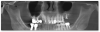

raevsku Опубликовано 10 июня, 2012 Автор Поделиться Опубликовано 10 июня, 2012 (изменено) А какая альтернатива в моем случае? Прикрепляю скриншот панорамного вида из КТ. http://i034.radikal.ru/1206/53/7684f0dbe00bt.jpg Изменено 10 июня, 2012 пользователем raevsku Ссылка на комментарий